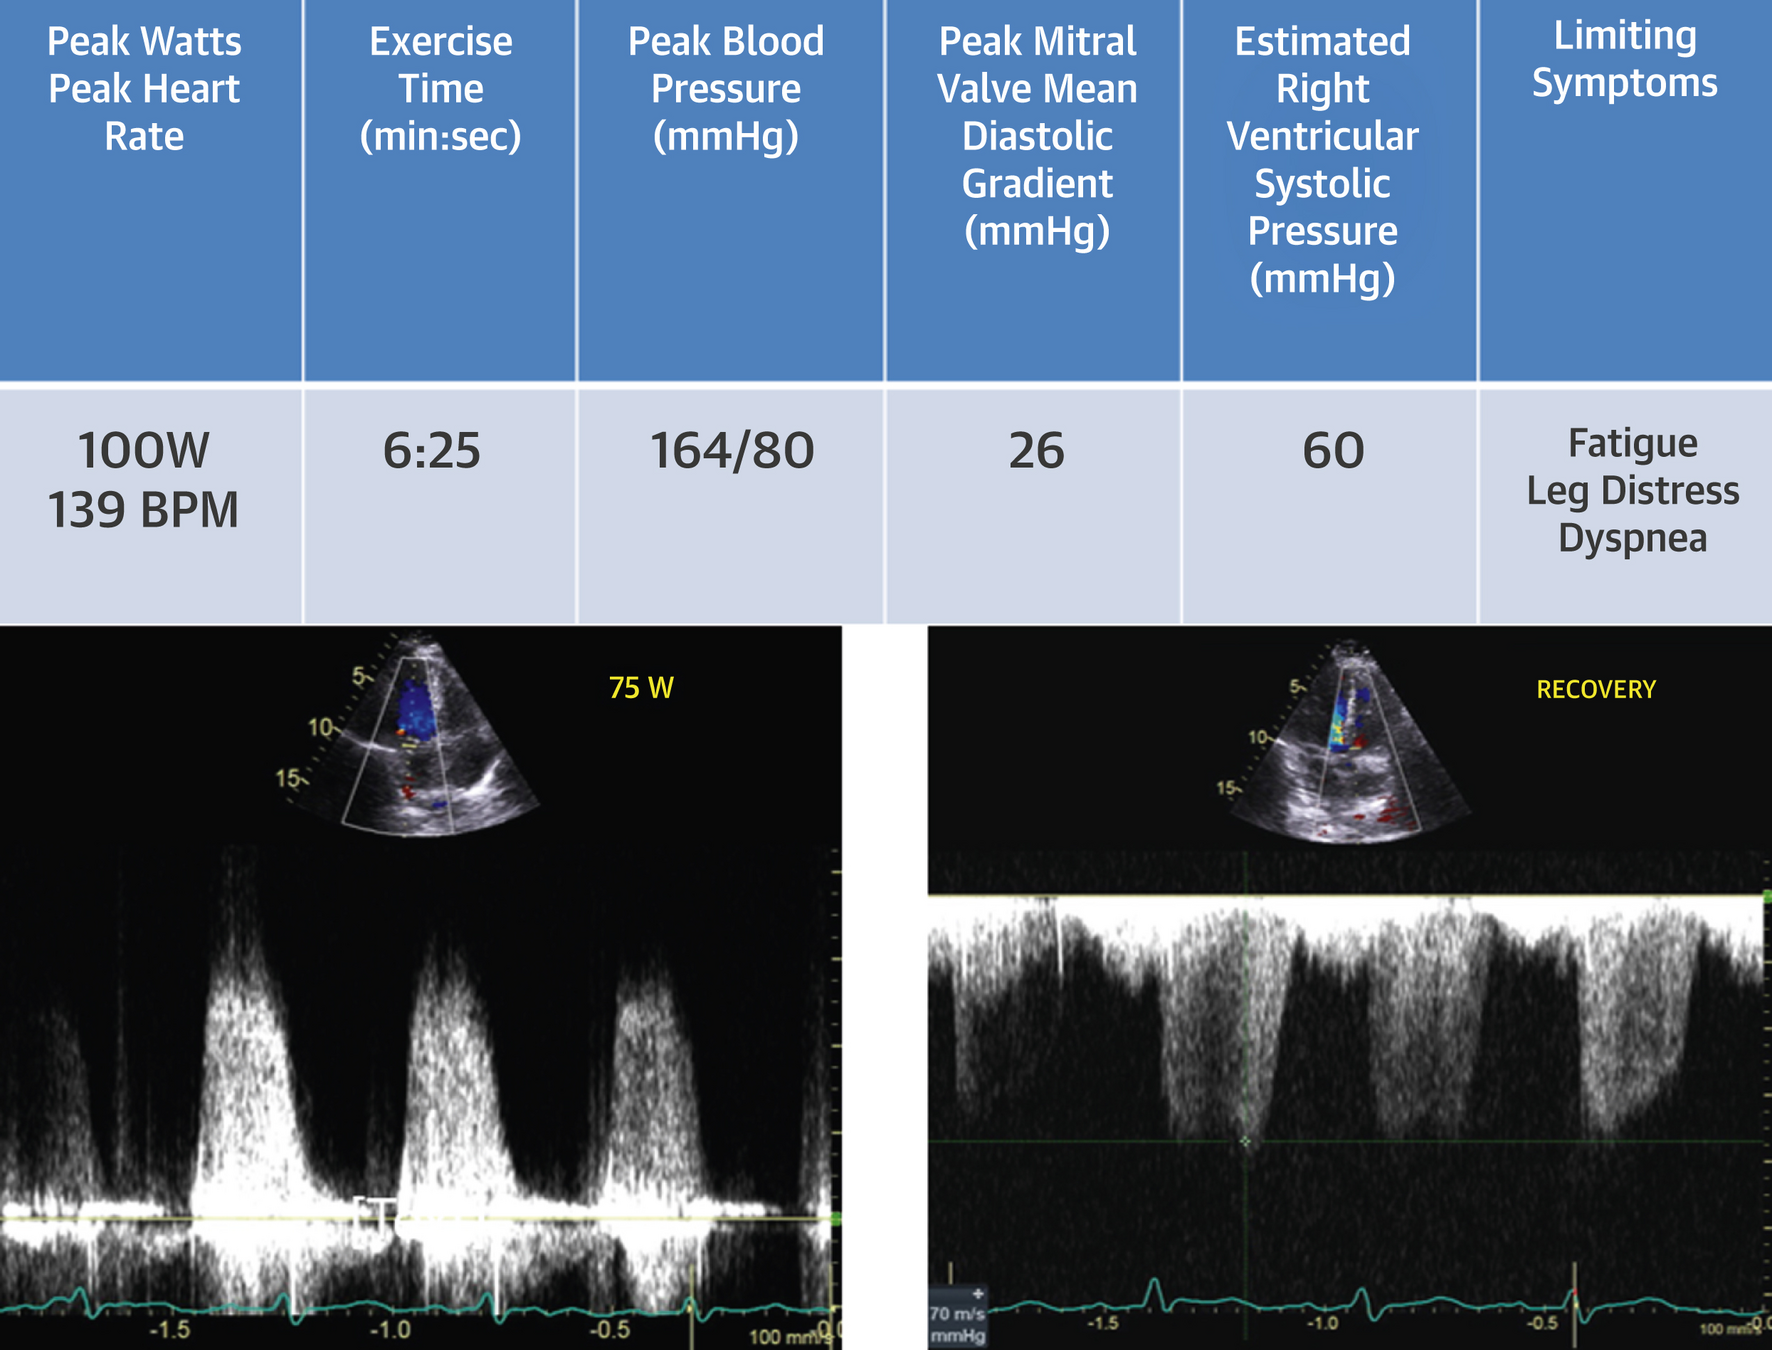

Case

• RFR: dyspnea

• 58-year-old female

• PHT 141 ms, MVA 1.6 cm2 (Mod MS)

• Mild to moderate regurgitation

Wiley BM, et al. (2020) Lung Ultrasound During Stress Echocardiography Aids the Evaluation of Valvular Heart Disease Severity. JACC Cardiovasc Imaging 13:866-72.